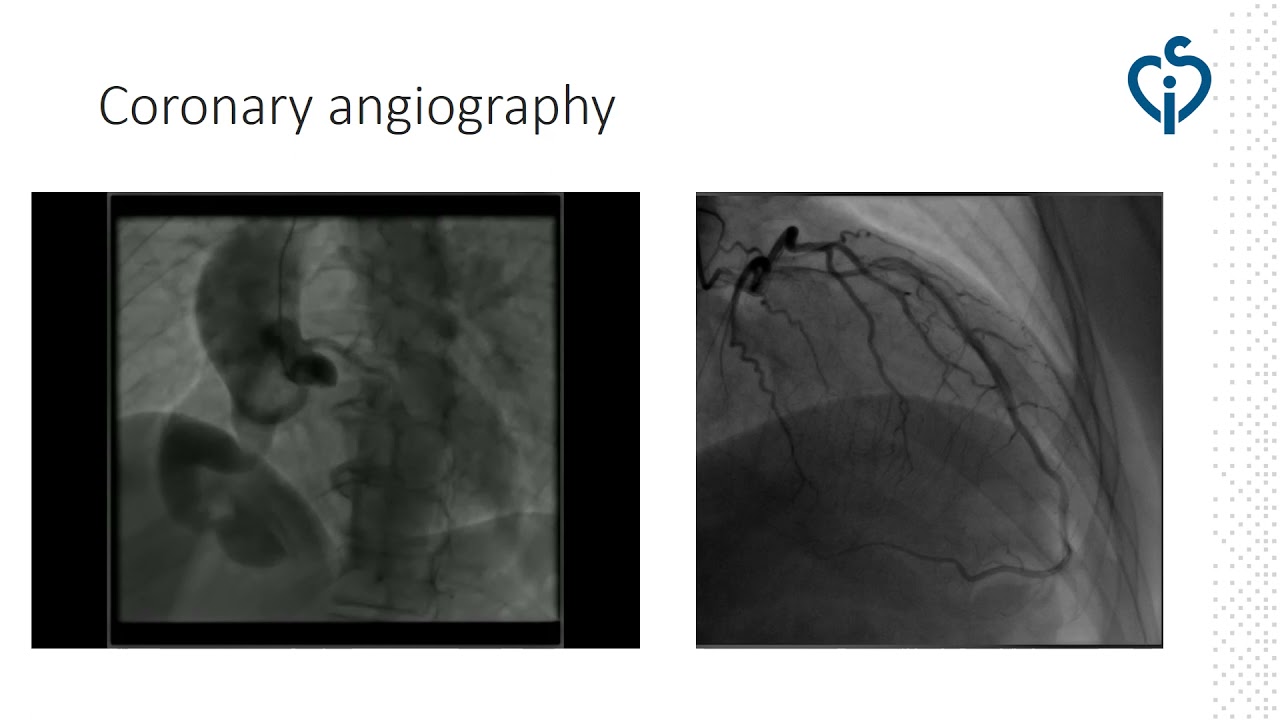

Transcatheter closure of recanalized large coronary-cameral fistula.

By: Lyubomir Dimitrov, National Heart Hospital, Sofia, Bulgaria